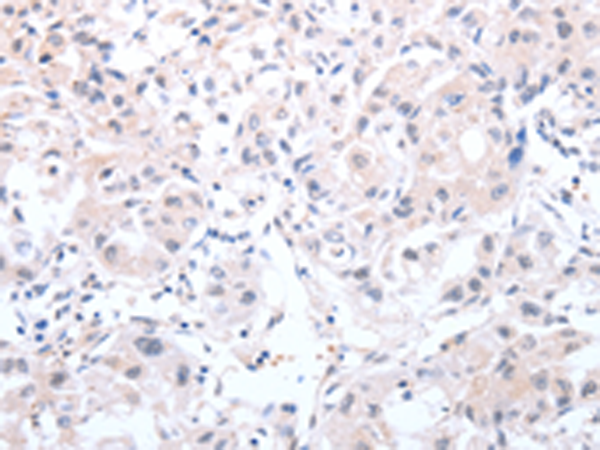

分类: 科研抗体货号: P11147别名: TYH; DYT14; DYT5b应用: IHC反应种属: Human